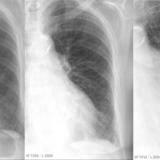

peribronchial cuffing

peribronchial cuffing bef and after

Date: 01/06/2018

Views: 6842